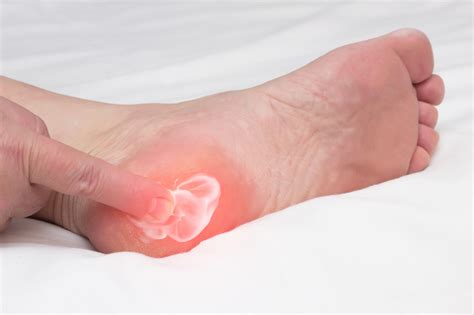

The primary symptom of a heel spur is pain in the heel, particularly in the morning or after periods of rest. Other symptoms may include:

• Pain that worsens with activity

• Swelling and tenderness in the heel area

• Difficulty walking or standing for extended periods